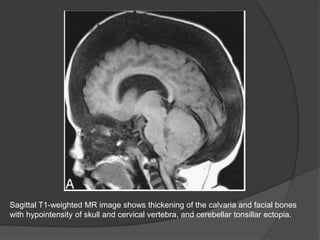

Sagittal T1-weighted MR image shows thickening of the calvaria and facial bones

with hypointensity of skull and cervical vertebra, and cerebellar tonsillar ectopia.

Sagittal T1-weighted MRimage shows thickening of the calvaria and facial bones with hypointensity of skull and cervical vertebra, and cerebellar tonsillar ectopia.